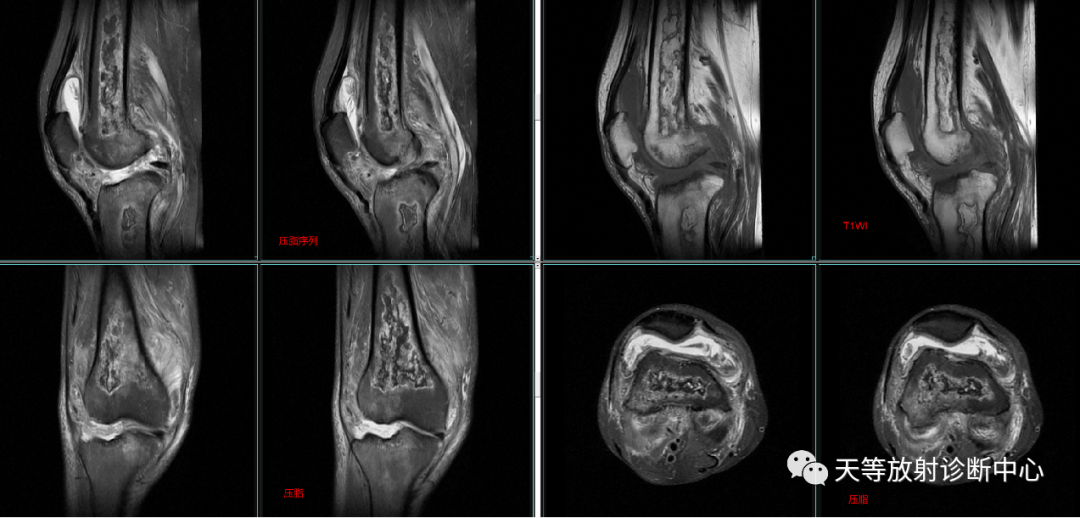

(3)病灶边缘呈迂曲的长T1信号带。T2WI分为2层,内层呈高信号带,反映充血水肿和肉芽组织;外层为低信号硬化带。

(4)病灶呈多发,形态不规则,并有融合趋势,呈典型“地图”样。

典型征象是病灶边缘呈“三环征”,由外向内,T1WI呈低-高-低,压脂T2WI 高-低-高。

地图样改变,周围不规则线状样影包绕。